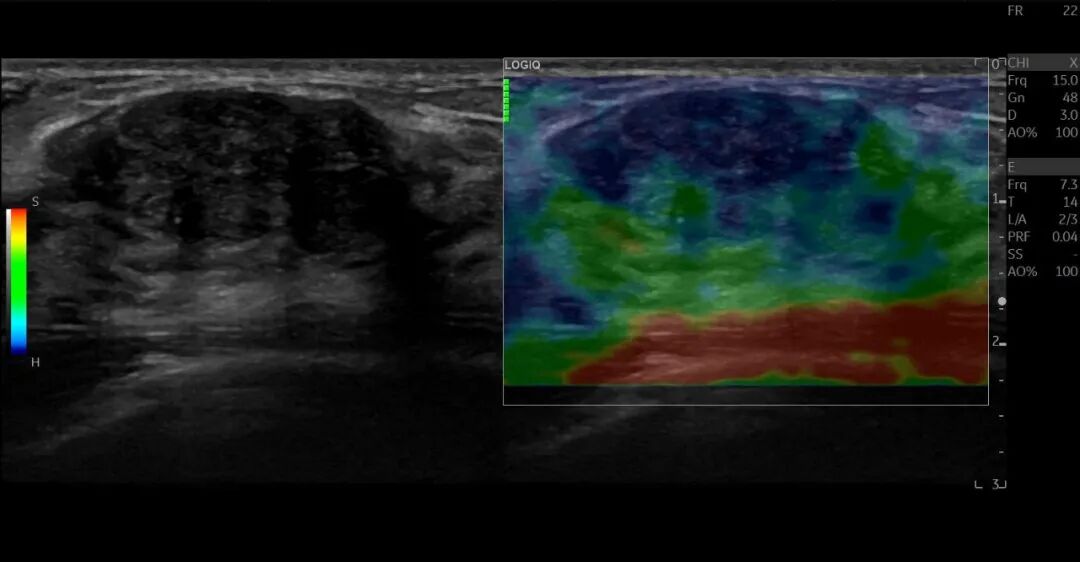

以GE医疗LOGIQ E11为例,其可以利用超声造影、剪切波弹性及应变弹性成像提供病灶血流灌注、弹性图和质地软硬定量数据,助力乳腺病变的诊断和治疗评估。加之,LOGIQ E11具备穿刺针增强技术,可专门针对穿刺针进行增强显示;帮助清晰显示穿刺针针尖和针道,为超声引导下的乳腺占位安全、精准、微创消融提供有力的保障。由于乳腺疾病发病率较高,用介入超声引导治疗后,如果再次发生病变,还可以二次治疗甚至三次治疗。微创消融技术的安全性高,通过大样本的循证医学表明,并发症要显著低于传统手术的发生率与严重程度。介入手术的预后效果也能达到患者满意。对于女性患者来讲,介入超声引导治疗是一项科学、规范、微创的新技术。